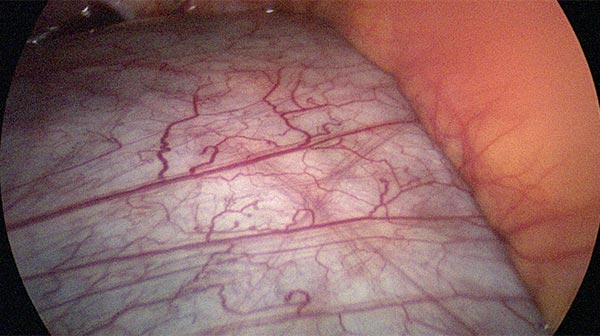

Blick vom Nabel zum rechten Oberbauch mit Leber und Gallenblase. Im Mesenterium des Dünndarms weitere durchscheinende Zysten.

Das Peritoneum zur Bauchhinterwand wird eröffnet und alle Zysten schrittweise aus der Umgebung ausgelöst und entfernt.